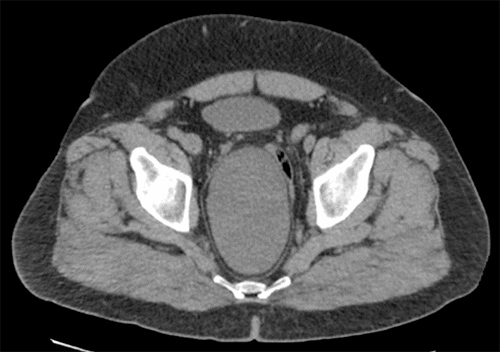

The patient is a 66-year-old White male with a medical history of morbid obesity who presented to the outpatient surgery clinic with swelling to the right gluteal area. He demonstrated a 10 × 12 cm soft tissue mass on physical examination along the right inferior gluteal fold. Though the lesion was clinically consistent with a lipoma, applying gentle pressure to the mass resulted in referred pain and pressure within the abdomen. There was no cough impulse, but movement was noticed in the abdomen when reducing the swelling. The differential diagnosis was expanded to include a soft tissue lesion extending from the pelvis and/or a hernia defect. Given the patient's habitus and equivocal physical exam findings, an ultrasound was performed, which noted a hypoechogenic area in the gluteal fold region appearing to herniate through a defect with coughing followed by spontaneous reduction. (Figure 1A) The contralateral region was imaged without similar findings, raising the suspicion of a gluteal hernia versus a gluteal lipoma. Due to poor compliance, the patient was initially lost to follow-up but returned to the clinic within a year with complaints of a symptomatic increase in the size of the swelling. A CT scan of the pelvis demonstrated a large well-circumscribed oval mass measuring 11.9 × 7.5 × 14.9 cm in the deep pelvis posterior and lateral to the rectosigmoid colon extending into the ischiorectal fossa on the right side. The internal density of the mass was 17 Hounsfield units. It appeared to be a cystic fluid collection with  possible blood or proteinaceous debris (Figure 1B and Figure 1C).

B) CT imaging of pelvis showed large, well-circumscribed oval mass in deep pelvis posterior and lateral to rectosigmoid, which extended into right ischiorectal fossa. Measured 11.9 × 7.5 × 14.9 cm. Internal density of mass was 17 Hounsfield units.

C) CT imaging of pelvis showed large, well-circumscribed oval mass in deep pelvis posterior and lateral to rectosigmoid, which extended into right ischiorectal fossa. Measured 11.9 × 7.5 × 14.9 cm. Internal density of mass was 17 Hounsfield units.